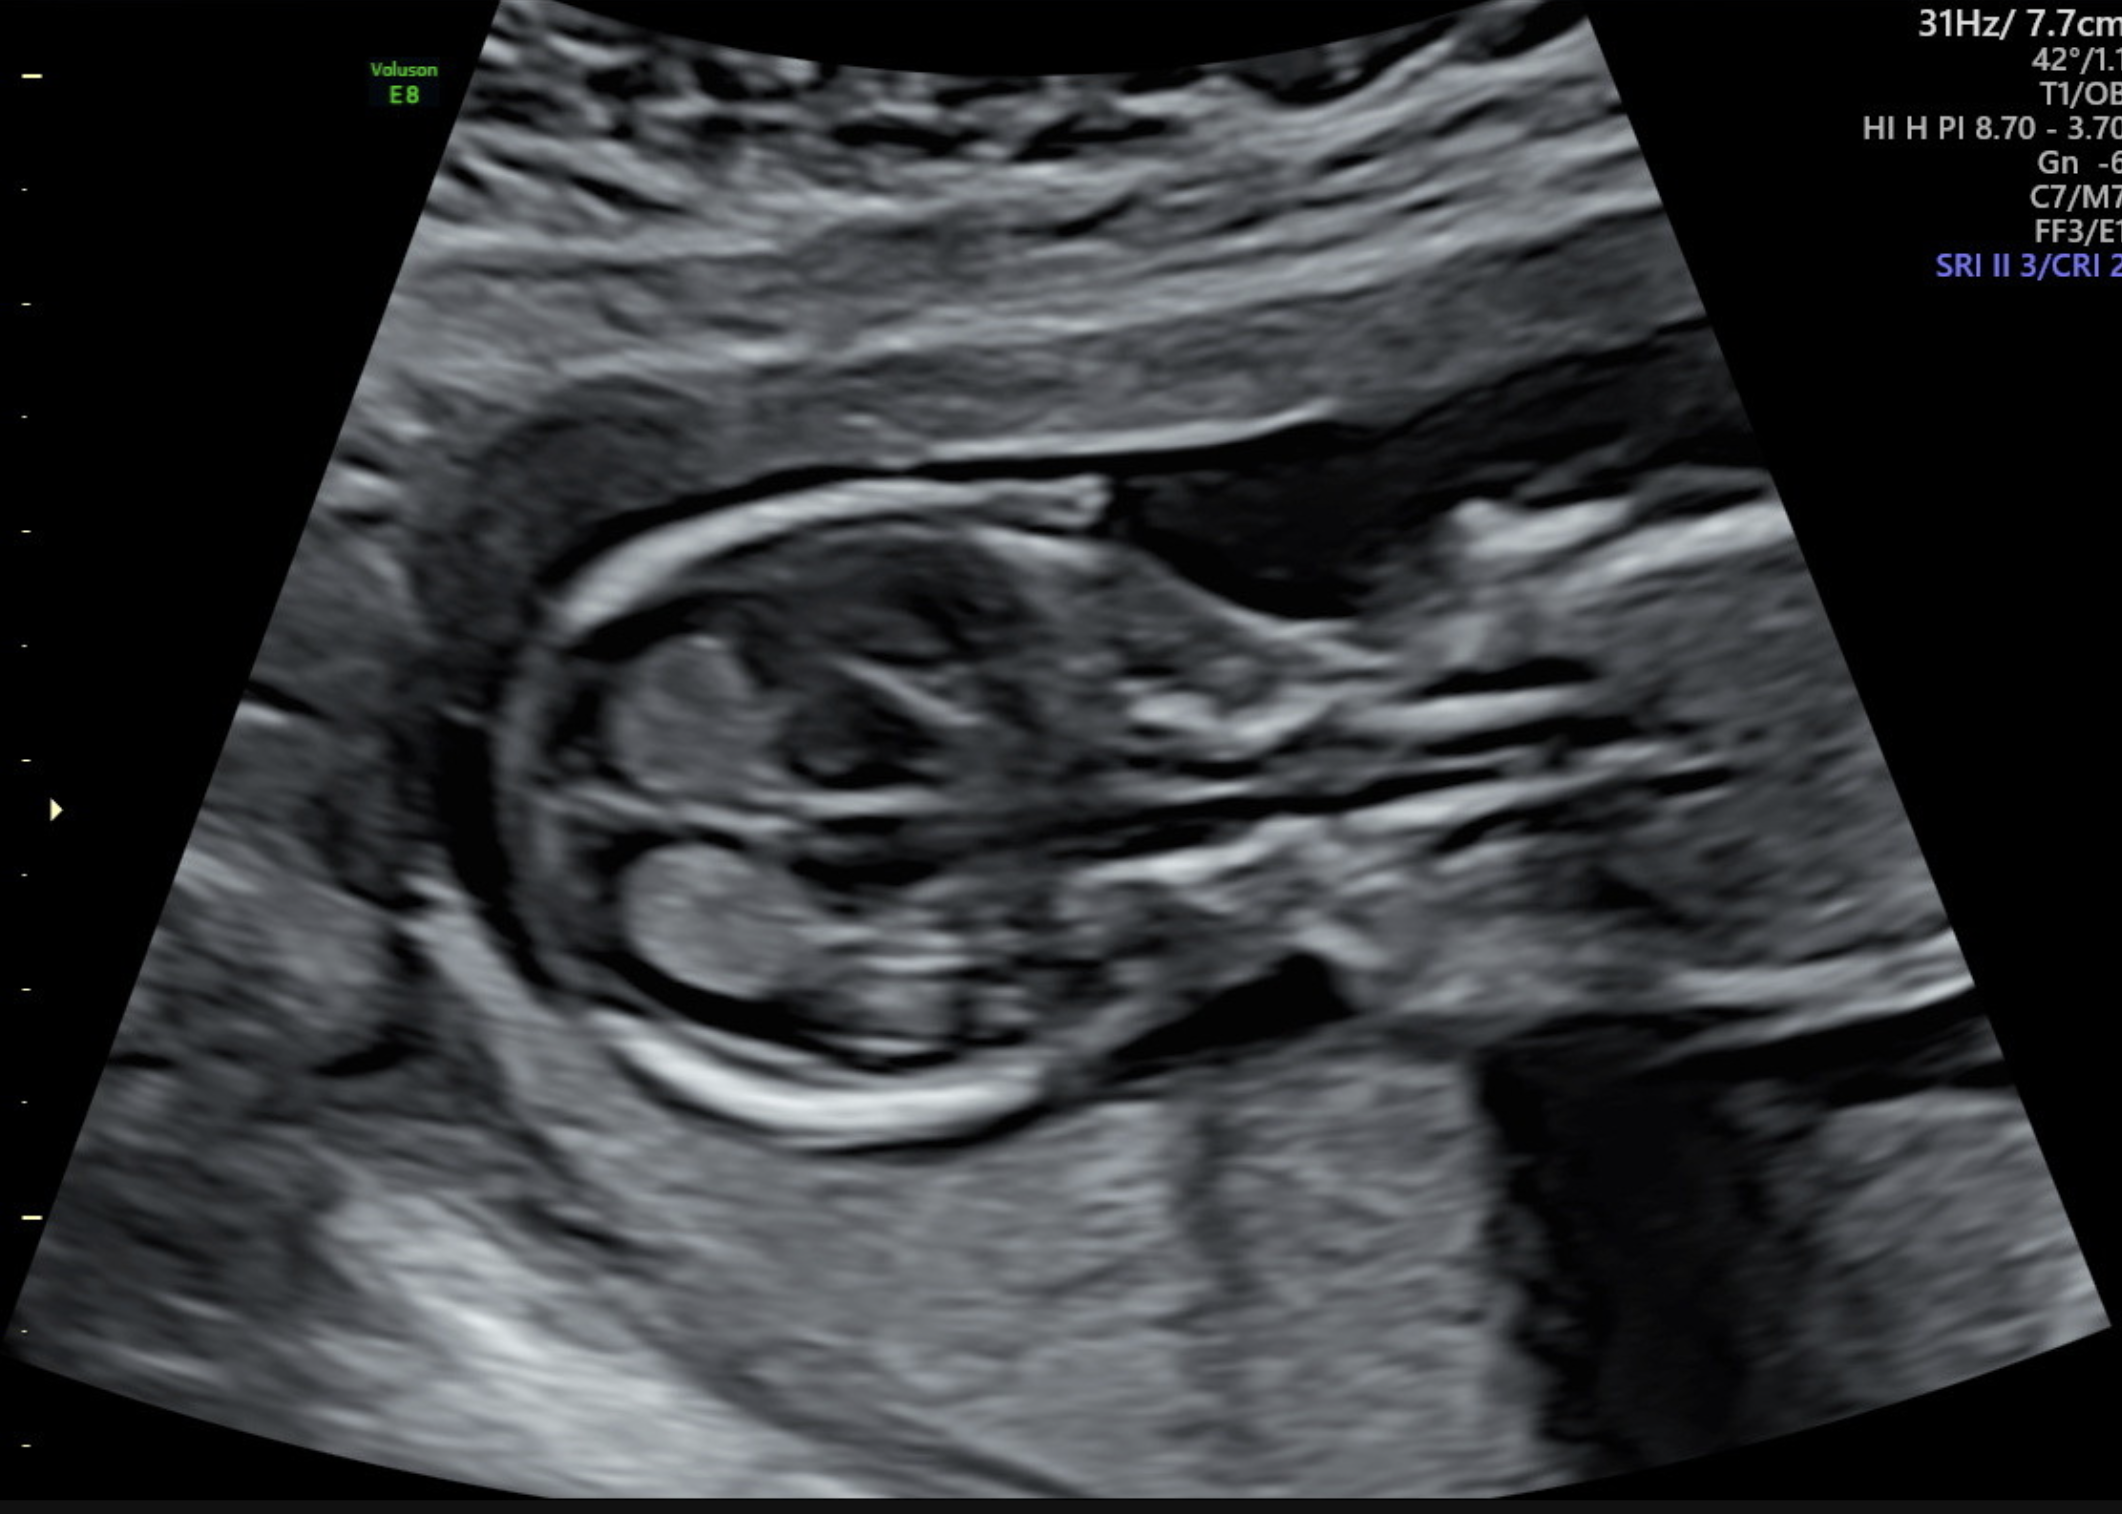

Nuchal Translucency is the Sonographic appearance of the normal fluid space behind the head and neck of the fetus. This fluid is visualised in the first trimester of pregnancy.

A Nuchal Translucency Scan is also a first trimester screening ultrasound. The examination offers assessment for chromosomal anomalies. The test suggests which pregnancies are at a higher risk of abnormalities and may need further investigation.

The extra fluid and Nuchal Translucency measurement tends to be thicker (>3mm) in a baby that may be associated with chromosomal abnormalities. It can be compared with what is expected for a baby of the same size (Nuchal Translucency normal range).

The Ultrasound is a very time sensitive scan and the optimum time for performing this examination is between 12 weeks and 13 weeks 6 days as many cranial anatomical features which are being assessed won’t be detected until then.